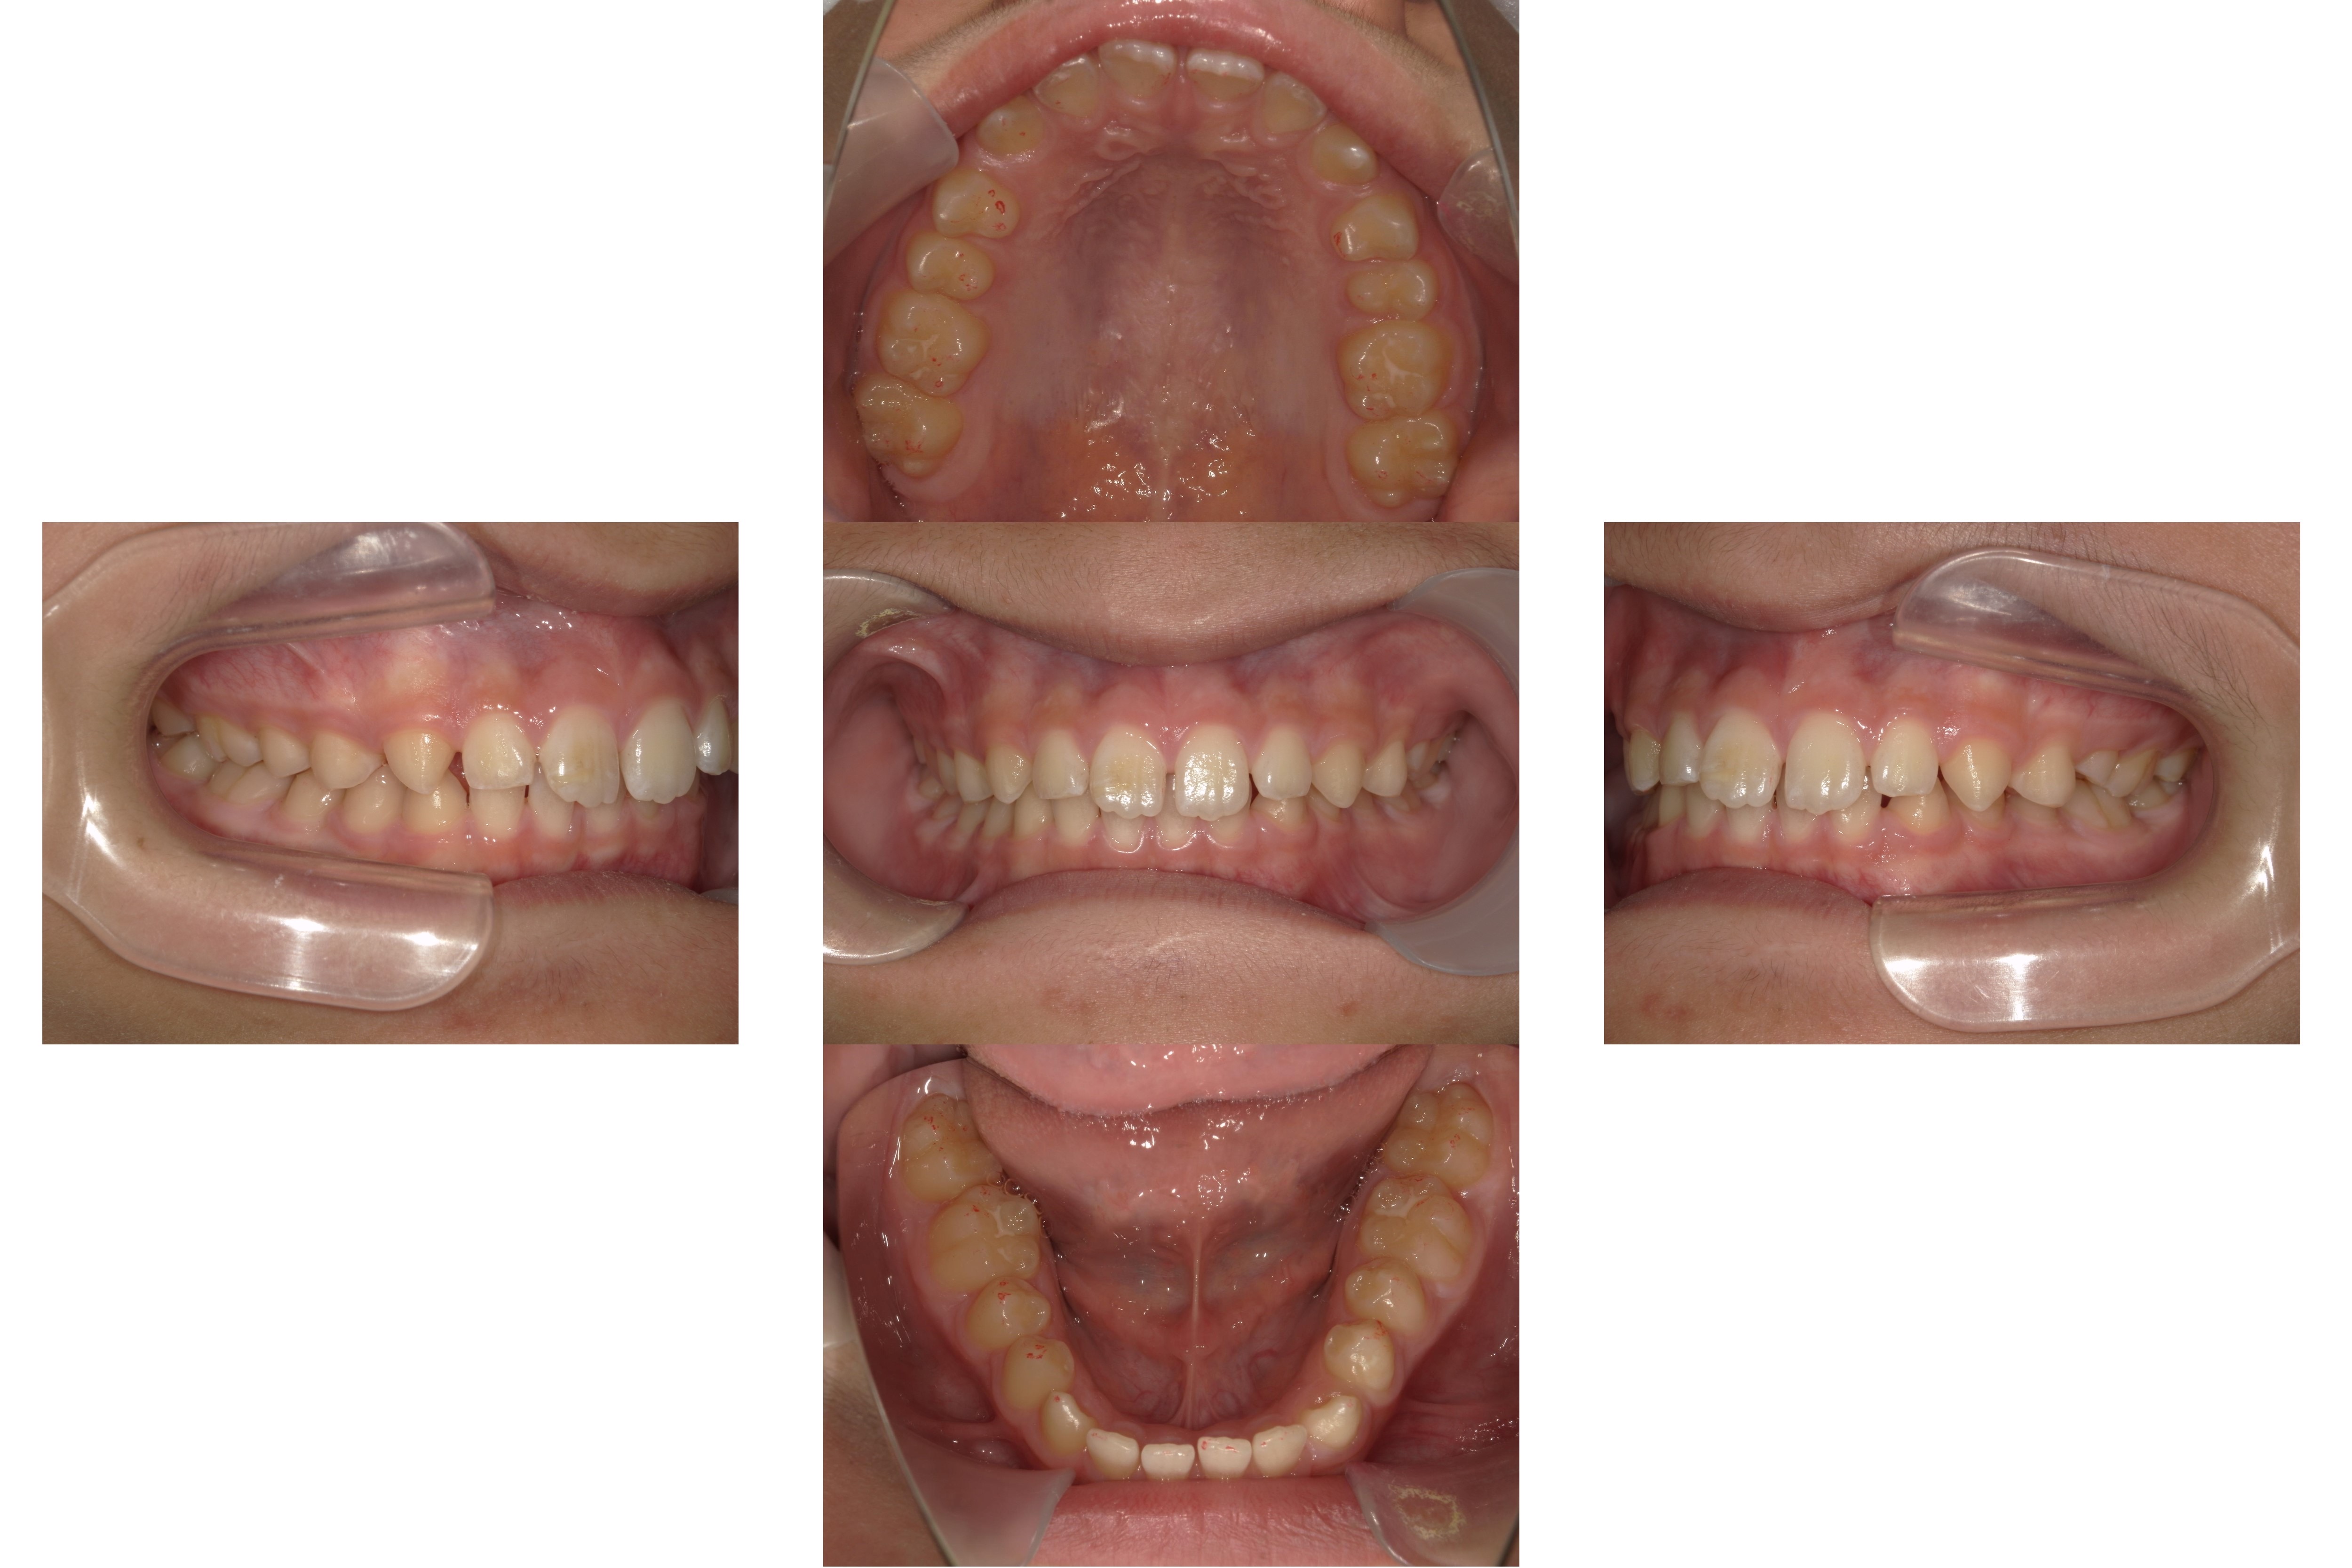

治療前

治療後

診断:過蓋咬合、空隙歯列

期間:1年半

内容:インビザラインプレミアム

費用:85万円